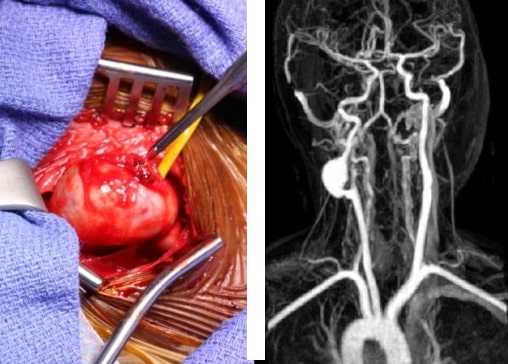

На основании дооперационной ангиографической картины, анализа геометрии аневризм мы разделили их на мешотчатые, фузиформные (веретенообразные) и «фузиформноподобные» аневризмы (рис. 1).

Рис. 1. Виды аневризм: А — мешотчатая, Б — фузиформная, В — фузиформноподобная

К фузиформноподобным мы отнесли те случаи, когда ветви СМА были вовлечены в структуру шейки или отходили непосредственно от мешка аневризмы, что снижало радикальность операции и повышало риски развития как интра-, так и послеоперационных осложнений (рис. 2).